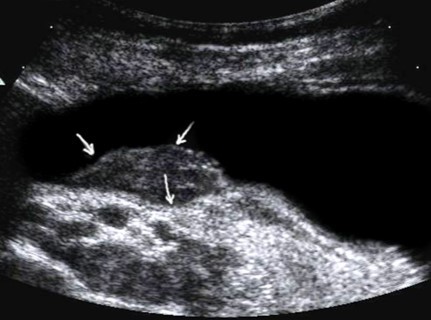

The polypoid type of gastric cancer was observed in 3 (4,9±2,8%) cases, the ulcerative type – in 18 (29,5±5,8%), the infiltrative ulcerative type – in 27 (44,3±6,4%) and the diffuse infiltrative type – in 13 (21,3%±5,2%) cases respectively (Table 2). On the echogram, the tumor was

Visualized as a polypoid formation on a wide base above the gastric mucosa of a non-uniform structure, an irregular surface (Figure 5, Figure 6, Figure 7).

Figure 6.The gastric carcinoma for T3 stage. The tumor is visualized as a polypoid formation on a wide base above the gastric mucosa of a non-uniform structure, an irregular surface (arrows).